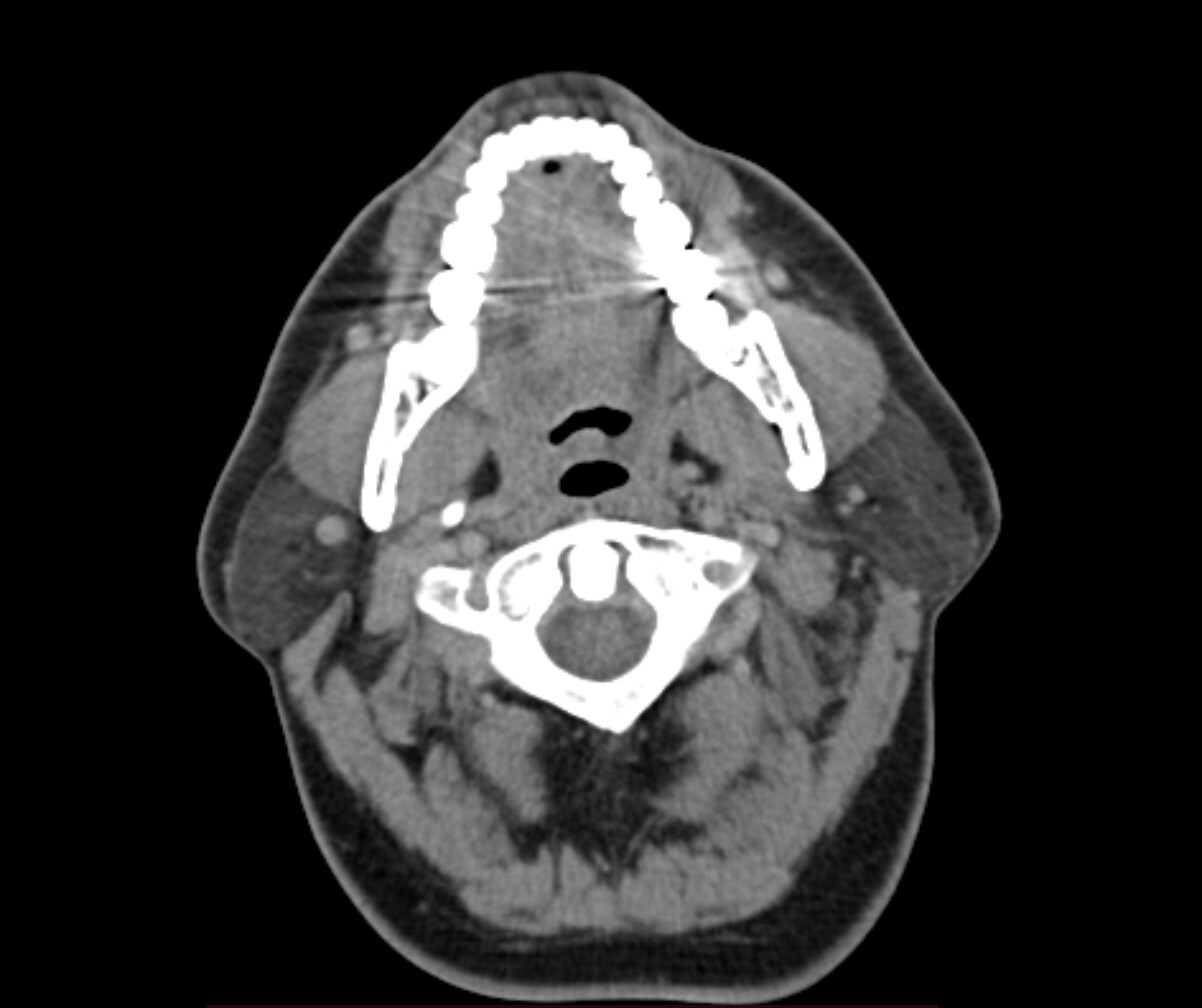

Typically, in the context of vascular ES, the most relevant view is of C1 in the axial view. I’ve attached my own imaging to help you know what to look for. It’s the top vertebrae with a white circle in the top middle:

Hey all thanks, will take a look at the video shortly, in the meantime here’s the axial view, I think.

It’s hard to see, but I believe your your right IJV is wedged between your posterior digastric and C1. The right styloid is not in contact with anything, at least at this level.

Left IJV appears to have some compression against C1. Left styloid is not present at this level.